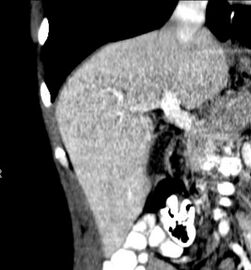

-

صورة مقطعية محورية تظهر أوردة كبدية شاذة تنتشر على السطح الأمامي تحت المحفظة للكبد.[73]